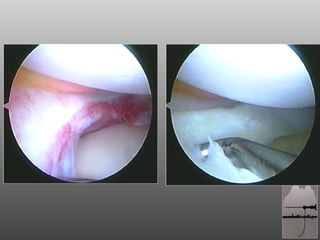

RAGAZZO DI 18aa, ATTIVO (CALCIO DILETTANTI) A 16aa SUTURA MENISCALE CORPO MENISCO ESTERNO OUT-IN  A 17 BLOCCO ARTICOLARE POST-TRAUMA: ARTROSCOPIA

RAGAZZO DI 18aa,ATTIVO (CALCIO DILETTANTI) A 16aa SUTURA MENISCALE CORPO MENISCO ESTERNO OUT-IN A 17 BLOCCO ARTICOLARE POST-TRAUMA: ARTROSCOPIA

Indicazioni Lacerazione mediale o laterale non riparabile del menisco, con necessità di meniscectomia parziale Integrità delle inserzioni anteriore e posteriore del menisco  Bordo integro sull'intera circonferenza del menisco LCA integro Arto inferiore in asse Danno condrale max 2° Pazienti in grado di comprendere e seguire un programma di riabilitazione post-operatoria

Indicazioni Lacerazione medialeo laterale non riparabile del menisco, con necessità di meniscectomia parziale Integrità delle inserzioni anteriore e posteriore del menisco Bordo integro sull'intera circonferenza del menisco LCA integro Arto inferiore in asse Danno condrale max 2° Pazienti in grado di comprendere e seguire un programma di riabilitazione post-operatoria